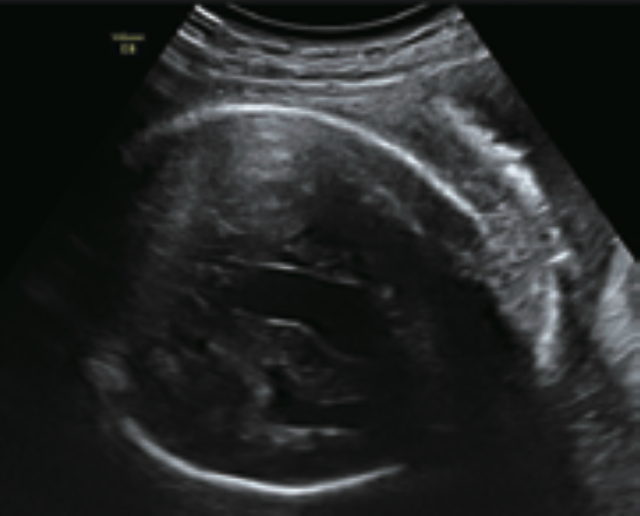

硬膜動靜脈瘻管(Dural Arteriovenous Fistula)是少見的疾病,產前診斷更不常見,通常需要彩色都卜勒超音波與磁振造影的共同協助。以下報告一位個案:37歲,第二胎,前胎足月自然生產,無特殊異常。本次懷孕34週時,超音波發現胎兒腹水、肋膜積水、心臟擴大(圖一)以及前置胎盤。胎兒腦部發現一囊狀構造(圖二),color Doppler顯示血流豐富(圖三),超音波初步臆斷為Vein of Galen aneurysmal malformation (VGAM)。產前磁振造影進一步發現右側大腦表面有異常鼓脹的血管,延伸至右側大腦靜脈及後方直竇,另外兩側頸動脈、中腦動脈和椎動脈也異常擴張(圖四)。兩側大腦有毀壞性病灶及腦組織萎縮,尤其以右側額葉最嚴重。同時也有發現左側基底核出血及腦室出血,以及頸靜脈怒張、肋膜積水、腹水、肝臟腫大等心臟衰竭徵兆(圖五)。新生兒腦部磁振造影發現除了上述發現以外,外頸動脈以及中腦膜動脈(圖四)也有異常擴張。綜合影像學發現,此個案的診斷為顱內硬膜動靜脈瘻管合併兩側大腦組織毀壞性病灶、左側基底核出血、及續發心臟衰竭。

圖一:心臟衰竭與肋膜積水